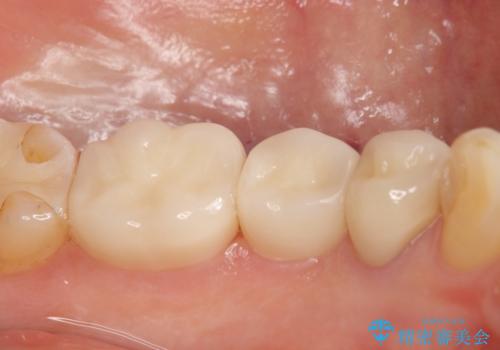

- 左下の詰め物が取れてしまったので治療したい、ついでに銀歯も白くしたいといらっしゃった方の症例です。

銀歯及び虫歯を除去後、オールセラミッククラウンによる補綴を行いました。

今回用いたオールセラミッククラウンはジルコニアフレームという白い素材の上にセラミックを盛っているため、審美性が非常に高いのが特徴です。

また、ジルコニアは人工ダイヤモンドの材料にも使われているほど高い強度を持っており、そのためオールセラミッククラウンは審美性だけでなく、奥歯やブリッジの補綴も可能とするクラウンです。